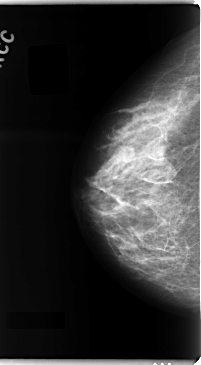

C_0097_1.RIGHT_CC

RIGHT_CC LINES 4736 PIXELS_PER_LINE 2608 BITS_PER_PIXEL 12 RESOLUTION 50 NON_OVERLAY